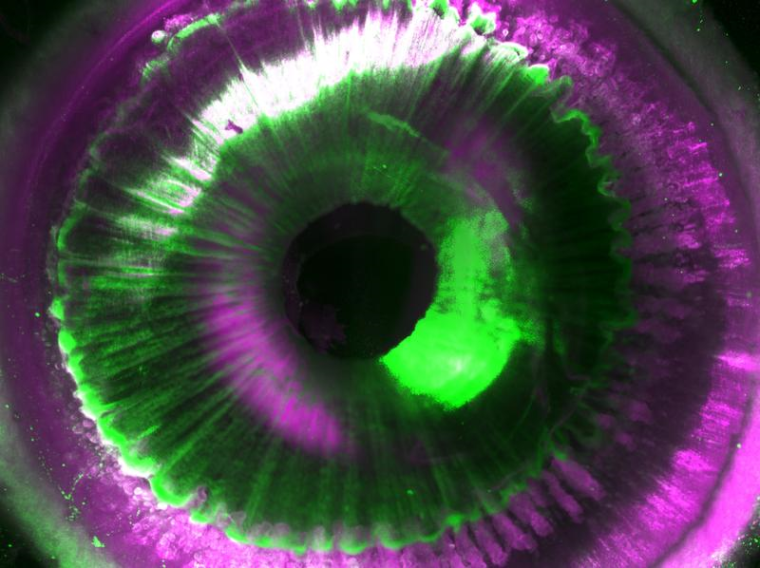

Erstmals gelang es Wissenschaftlern, intakte menschliche Organe durchsichtig zu machen. Die transparenten Organe ermöglichen eine dreidimensionale Kartierungen auf Zellebene.

Mittels mikroskopischer Bildgebung konnten sie die zugrunde liegenden komplexen Strukturen der durchsichtigen Organe auf zellulärer Ebene sichtbar machen. Solche strukturellen Kartierungen von Organen bergen das Potenzial, künftig als Vorlage für 3D-Bioprinting-Technologien zum Einsatz zu kommen. Das wäre ein wichtiger Schritt, um in Zukunft künstliche Alternativen als Ersatz für benötigte Spenderorgane erzeugen zu können. Dies sind die Ergebnisse des Helmholtz Zentrums München, der Ludwig-Maximilians-Universität (LMU) und der Technischen Universität München (TUM).

Nachdem die menschlichen Organe, die post mortem vom Labor von Prof. Ingo Bechmann der Universität Leipzig bereitgestellt wurden, transparent gemacht worden waren, mussten die Wissenschaftlerinnen und Wissenschaftler zusätzliche Herausforderungen bewältigen: Die Bildgebung der Organe und die Auswertung der dabei entstehenden Datenmassen. Zunächst entwickelten sie daher gemeinsam mit Miltenyi Biotec ein neues Laser-Scanning-Mikroskop mit einer besonders großen Aufnahmekapazität namens „Ultramicroscope Blaze“. Mit diesem Mikroskop sind Aufnahmen von gesamten menschlichen Organen bis hin zur Größe einer Niere möglich. Anschließend entwickelte das Team zusammen mit Prof. Bjoern Menze von der TUM Deep-Learning-Algorithmen, um Abermillionen von Zellen in 3D analysieren zu können.